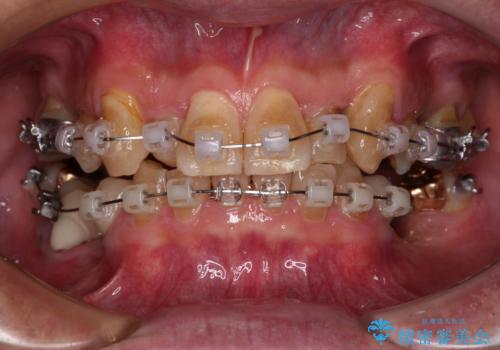

奥歯の欠損と前歯のデコボコを治したい インプラントと矯正治療の総合歯科治療

- 下顎両側の欠損と上顎前歯のデコボコを気にして来院された患者様です。

デコボコは今まで気にせずにいたそうですが、奥歯の欠損改善を機に、矯正治療に興味があるので、相談したいとのことでした。

奥歯に欠損が多く、矯正治療はやや難航することが予想されますが、患者様の希望もあり、上顎左右小臼歯を1本ずつ抜歯し、ワイヤー装置にて矯正治療を行うこととしました。

矯正歯科治療を行うに当たり、痛みや違和感を感じている歯の根管治療を行い、矯正治療中にインプラント埋入し、補綴治療と矯正治療を同時に終了できるように進めて行くこととしました。